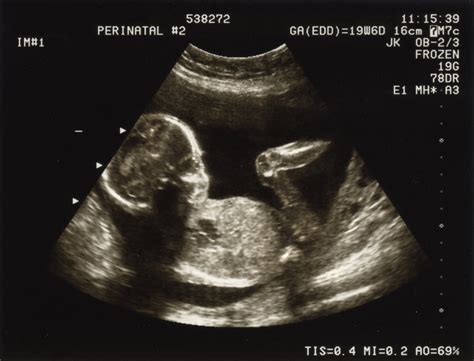

În urma ecografiei, medicul a explicat că fătul avea o circulară pericervicală, considerată o problemă nuanțată, deoarece mulți copii se nasc așa pe cale naturală. "În urma ecografiei, i-am explicat că fătul are o circulară pericervicală, ceea ce nu este o problemă acută pentru că mulți copii se nasc așa și pe cale naturală." Greutatea fătului era chiar mai mare decât era normal pentru 34 de săptămâni, neindicând o suferință fetală. Pacienta a fost rechemată la control în 2-3 săptămâni. "Mai mult, fătul avea o greutate chiar mai mare decât era normal la 34 de săptămâni, deci nimic care să îmi atragă atenția referitor la o suferință fetală și am rechemat-o la control dacă dorea la 2-3 săptămâni."

Pe 15 februarie, la Maternitate, pacienta a raportat o diminuare a mișcărilor fetale. O nouă ecografie a arătat că fătul se mișca și avea un puls normal (150-160 bătăi pe minut). "Pe 15 februarie s-a prezentat la Maternitate spunând că fătul nu mai mișcă cum misca. Am revăzut-o ecografic, ne-am uitat amândouă că fătul misca, avea puls 150-160 bătăi pe minut, i-am spus că este în regulă și i-am spus că dacă dorește să rămână sub supraveghere." Pacienta a fost internată la cererea medicului, fără a exista indicații clare pentru cezariană la 34 de săptămâni. "A rămas la cererea mea, am internat-o și a urcat pe secție. Copilul era ok la acel moment și nimic nu forța o cezariană la acel moment, la 34 de săptămâni."

Din păcate, situația a escaladat rapid. Pacienta a raportat mișcări fetale până la ora 11:30, iar la ora 15:00, în timpul monitorizării, fătul nu mai prezenta semne vitale. "Pacienta a zis că a simțit mișcări până la 11.30, iar la ora 15.00, când doamnele asistente au mers la monitorizare, fătul nu mai prezenta semne vitale." Medicul a descris cazul ca fiind atipic, menționând prezența a multiple circulară ale cordonului ombilical. "Eu nu am mai văzut așa ceva. Un copil cu atât de multe circulare. Erau două circulare cu nod în jurul gâtului, apoi o circulară tip eșarfă și alte două circulare în jurul stomacului care nu puteau fi decelabile la ecograf. Este un caz atipic, eu nu am mai văzut așa ceva." Operația de cezariană a avut loc după 19 ore de la internare, moment în care deja era prea târziu. "Operaţia a fost după 19 ore de aşteptare. Vă daţi seama prin ce am trecut, mai ales soţia, ea ştiindu-se cu copilul mort în burtă."

Mama susține că pe durata sarcinii a efectuat mai multe ecografii care nu au evidențiat probleme. "Mama îndurerată susține că pe durata sarcinii s-a prezentat la medic și a făcut mai multe ecografii care nu au reliefat nici o problemă a fătului:" "Medicii sunt de vină, pentru că nu mi-au făcut operația. Mă duc mai departe să se facă dreptate. Nu las lucrurile așa, am suferit prea mult pentru acest copilaș și el a suferit."